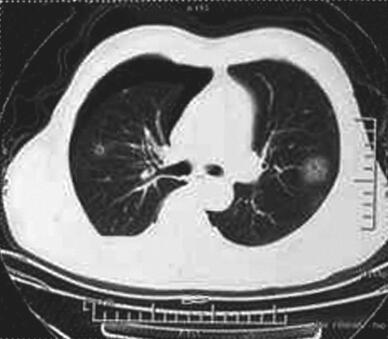

图3 2014年12月21日胸部CT

左舌段空腔病灶较前增大,左下叶基底段出现疑似空洞病灶,病灶周边可见斑片影,双侧气胸,以右侧为主